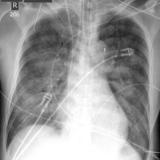

APE 6

+ IABP

Date: 01/13/2008

Views: 3523